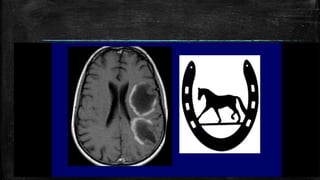

• #67 Empty delta sign. Postcontrast axial CT scan of the brain (A) shows the nonenhancing lumen of the superior sagittal sinus surrounded by enhancing dura (arrows). Nonenhanced axial CT scan of the brain (B) shows a hyperdense superior sagittal sinus (arrow) suggestive of thrombus within. This is called the ‘triangle sign.’ Sagittal reconstruction of a contrast-enhanced CT scan (C) shows filling defects in the superior sagittal sinus (long arrows) and in the straight sinus (thick arrow), suggestive of thrombus

• #69 g